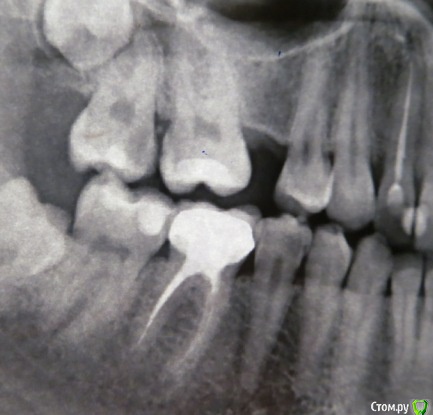

anaG2011 Опубликовано 27 июля, 2017 Поделиться Опубликовано 27 июля, 2017 (изменено) Здравствуйте!На верхних 6 и 7 зубах стояли пломбы с 2001г. Откололся кусочек 7ки.Врач высверлил старые пломбы. Каналы не вскрывали. На 7ке поставил "лечебную прокладку".Закрыл зубы временными пломбами. На холод-горячее-накусывание не реагируют. Скажите, пожалуйста, каким способом предпочтительнее восстановить 6 и 7 :пломбами или керамическими вкладками ?Какие минусы каждого из вариантов?(антагонист 7ки - недепульпир. зуб с пломбой 2001г.) Заранее спасибо. С временными пломбами: http://s016.radikal.ru/i337/1707/21/0e977cd9dd43.jpg До начала лечения: http://i057.radikal.ru/1707/b8/d717547654e5.jpg Изменено 27 июля, 2017 пользователем anaG2011 Ссылка на комментарий